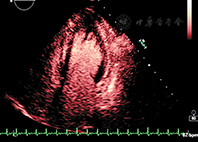

清晰地显示左心室心内膜边界是准确评价左心室功能的关键。国外临床试验表明,常规超声心动图检查时70%~90%的心血管超声图像不佳(图像质量不佳定义:在任何一个心尖长轴标准切面有2个或2个以上的连续心肌节段的心内膜结构不能清晰显示),通过使用造影剂后可明显提高诊断图像的解剖结构分辨率[15,16,17](图2)。在心脏解剖结构和功能异常状态判断存在疑问时也可考虑使用超声造影剂。当静息状态不能满意获得常规超声心动图图像时,造影剂用于左心室心腔造影尤其有帮助,这常见于肥胖、有肺部疾患、病情危重或接受呼吸机护理的患者。如果在这些患者中优化了换能器频率、扇扫宽度、图像深度和聚焦位置,心脏超声图像质量仍不理想,应当考虑使用造影剂。负荷超声心动图检查达峰值负荷时图像质量不理想的情况常较明显,此时使用造影剂将明显提高图像质量、增强判断信心和诊断准确性。此外使用造影剂将明显提高有经验和无经验医师解释图像的重复性和准确性[18,19,20]。